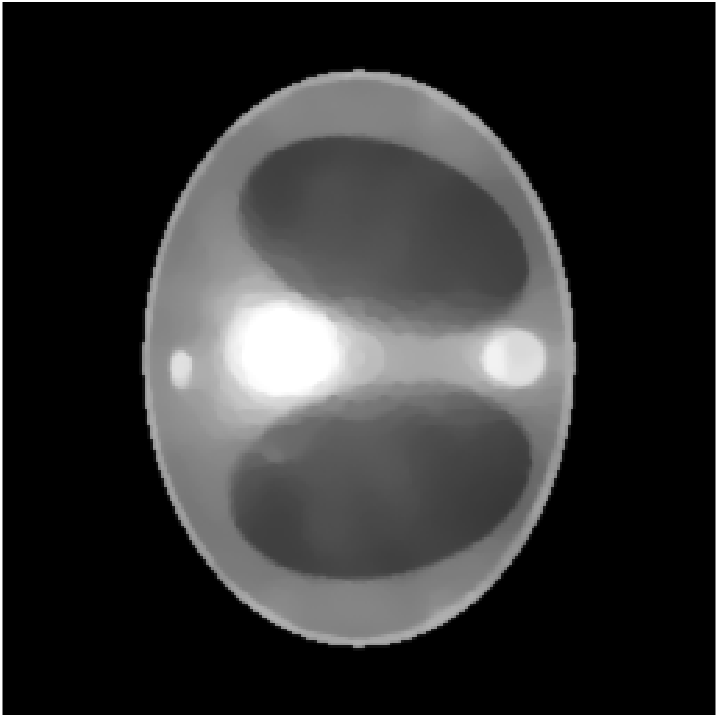

We assume to measure a total of photons and compute synthetic data from eq. 11 for a phantom electron density modeling a transversal slice of a human thorax. The phantom (see fig. 2(b)) consists of characteristic functions of ellipses of different sizes and opacities and is a modified version of an earlier phantom which was used in [12]. It is 28.4 cm resp. 21.3 cm wide at its largest and smallest diameters and its gray values are chosen as electron densities of materials typical in a human thorax [15, 3, 30].

In the reconstruction, a suitable choice for the regularization parameter is computed by the L-curve method. In fig. 3(e) we see that a reconstruction of the electron density from works well and the TV penalty term reduces the effects from the Poisson noise sufficiently. However, adding the component (fig. 3(f)) to the spectrum distorts the reconstruction. Due to the enormous noise level brought into the model by the component , the TV-regularized solution suffers from bad quality. Details are less visible or harder to localize and intensities of the different regions are altered complicating material recognition.

The method is tested for two synthetic phantoms; firstly, the thorax phantom already used in section 2. Figure 8 shows how the algorithm succeeds in decreasing the impact of the higher-order scattering. The ground truth is displayed in fig. 8(a). Expectably, the CT reconstruction (fig. 8(d)) is not accurate enough, but can be used as a prior to estimate the nonlinear weight function . Using , the CST reconstruction is computed. For comparison, we give both the solution of eq. 25 (without ) and eq. 26 (with ). As in section 2, eq. 25 cannot yield a useful reconstruction. The minimizer when is the Kullback-Leibler divergence (13) and is very noisy (fig. 8(b)) and using TV regularization, some noise can be filtered out, but only at the cost of losing small details of lower contrast (fig. 8(e)). As desired, applying to the data reduces the noise level, see fig. 8(c) and fig. 8(f) (with TV regularization). After applying , we use the norm as data fidelity measure. Densities and contrasts are accurately recovered and previously vanished details can be correctly located.